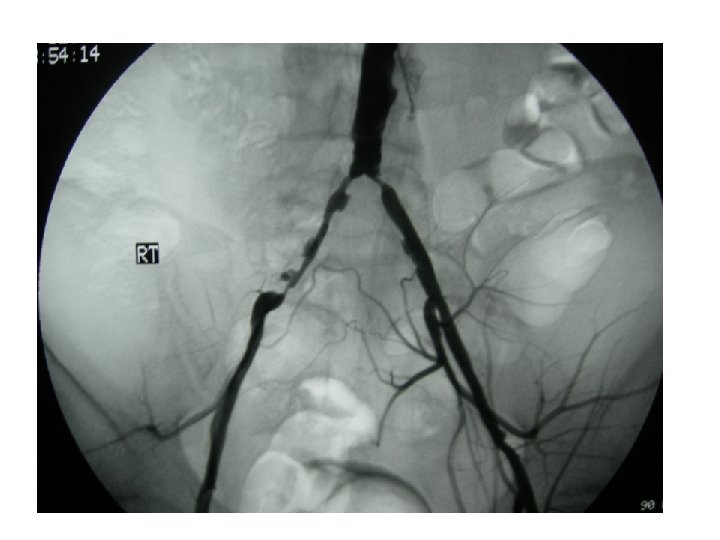

ΕΠΙΛΟΓΗ STENT Carotid angioplasty and stenting

ΕΠΙΛΟΓΗ STENT • • Carotid (self-expandable, braided or nitinol) Vertebral (balloon expandable) Subclavian (balloon expandable) Inominate (balloon expandable) Renal (balloon expandable) Aorta (nitinol, balloon expandable) Common Iliac (balloon expandable, nitinol) Ext. Iliac (nitinol)

ΕΠΙΛΟΓΗ STENT • • • Internal Iliac (balloon expandable) Common Femoral (nitinol) Deep Femoral (balloon expandable) SFA (nitinol, PTA only) Popliteal (sheet, coil nitinol, PTA only) Infrapopliteal (unknown)